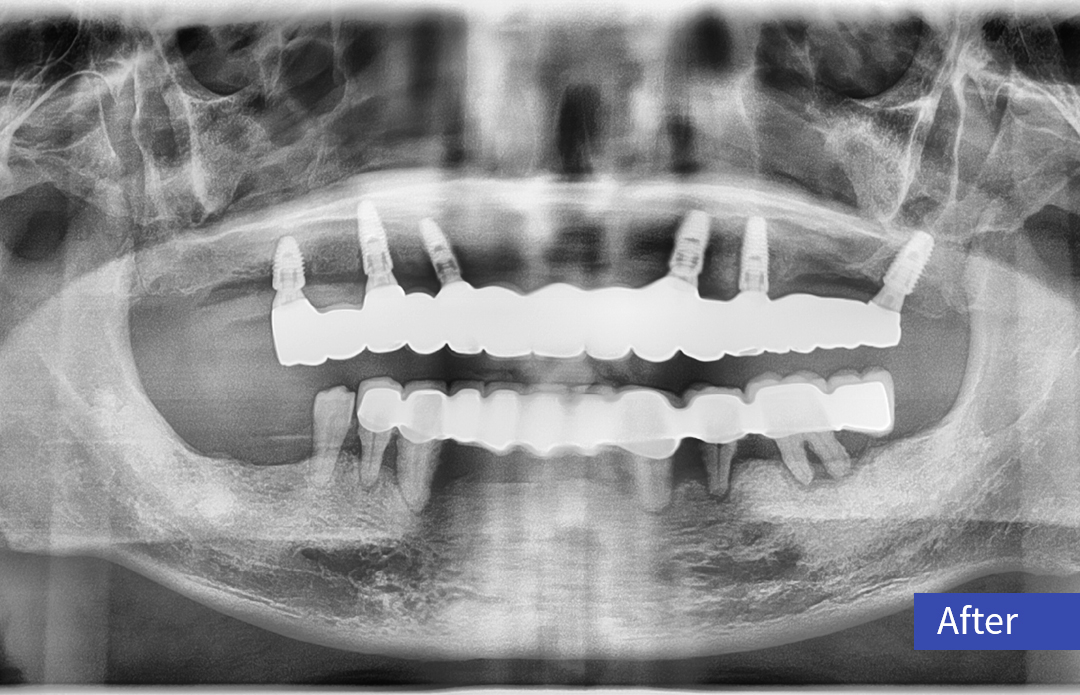

【病例分享】| 利多齿种植病例——全口即刻负重

全口即刻负重一例

病例分享 | 全口即刻负重一例